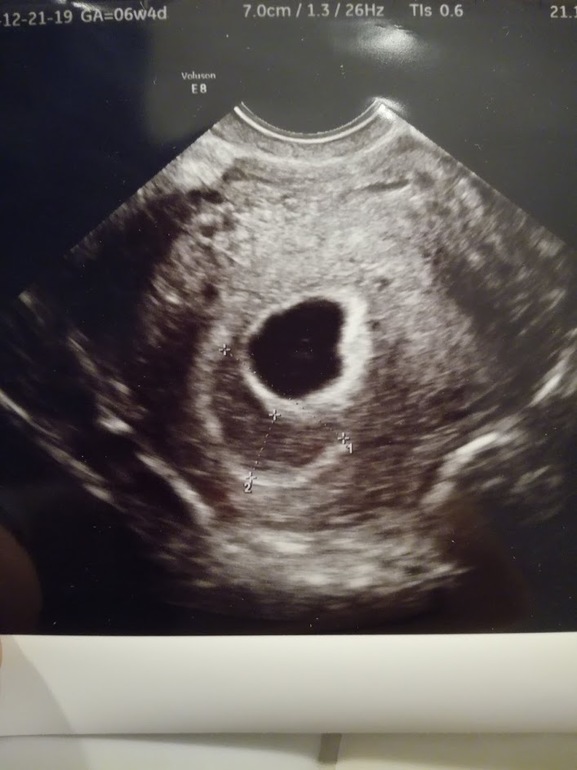

Вдогонку к моему прошлому посту о ЗБ и В - прикрепляю то самое УЗИ, через пару дней после которого случилось замирание (а может даже и через несколько часов после УЗИ - возможна погрешность из-за разных аппаратов).

Только после печального исхода до меня дошло, что гематома просто огромная по размерам.. и так близко от ПЯ. Это отслойка?

УЗИстка заверила, что у меня все хорошо и проверять ничего дополнительно не нужно (даже следить за прогестероном, т.к. мол и ЖТ и желточный мешочек хорошего размера). А Г даже не посмотрела фото и просто прописала параверин, если будут боли.